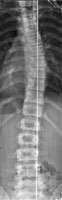

Возможность использования топографического мониторинга состояния больных сколиозом взамен рентгена была изучена на основе клинического материала школы-интерната №133 для детей больных сколиозом г.Новосибирска, где, начиная с 1995 года, проводились ежегодные обследования на ТОДП постоянного контингента больных параллельно с рентгеном. Среди больных по характеру течения заболевания выделены 3 группы: СФ - стабильная форма сколиоза, УПФ - умеренно прогрессирующая, БПФ - быстро прогрессирующая форма. Пример наблюдения больной с быстро прогрессирующей формой сколиоза приведен на рисунках ниже.

9,0 лет 10,4 лет 10,8 лет 11,4 лет 12 лет

PTI=1,0; Cobb=10° PTI=1,3; Cobb=17° PTI=1,9; Cobb=23° PTI=2,9; Cobb=38° PTI=3,6; Cobb=55°

За трехлетний период наблюдения в возрасте с 9 до 12 лет основная правосторонняя грудная дуга по углу Кобба спрогрессировала с 10 до 55°, т.е. средняя скорость прогрессирования составила 15° в год. Общий индекс нарушения формы дорсальной поверхности туловища PTI изменился с 1,0 (граница нормы и умеренно выраженных отклонений) до 3,6 (значительное отклонение). Следует обратить внимание, что в начале наблюдения туловище больной имело хороший баланс во фронтальной плоскости (вертикальная ось, проходящая через вершину межъягодичной складки, проходит также и через C7), а с возраста 10,8 лет стало явно нарастать нарушение баланса с отклонением туловища вправо, т.е. в сторону выпуклости основной дуги. Приведенный пример убедительно демонстрирует наглядность топографических данных и их большую информативность для решения задачи неинвазивного мониторинга состояния больных сколиозом.